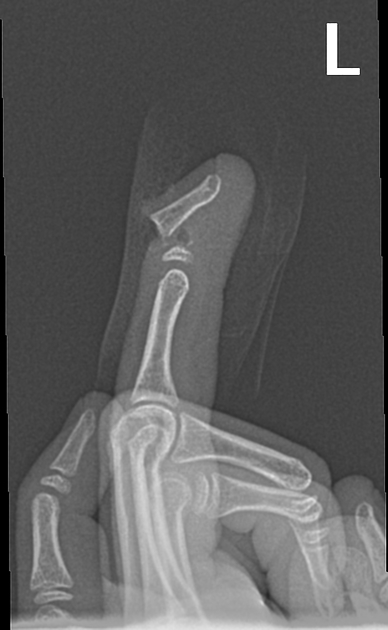

Describe this fracture?

A

SEYMOUR

- transverse fracture of distal phalanx at the physis in Peds

= SH1 or SH2

- typically crush injury in a door, etc.

• may have associated nail bed injury (avulsion of nail at germinal matrix) = OPEN #